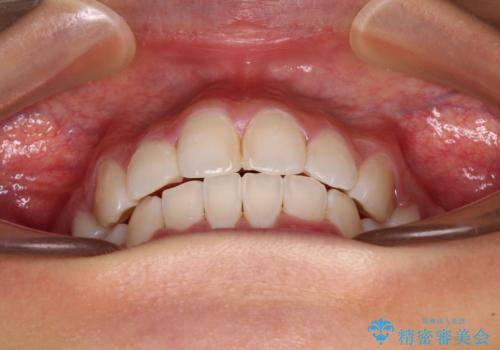

口元の突出感を改善 2年弱での抜歯矯正

治療前の上下正中はずれていましたが、骨格的な上下左右差はあまり認められなかったため、正中を揃えて治療を終えることができました。

1年半ほどで治療を終えることができるとは我々も想像しておらず、患者様には大変満足していただきました。